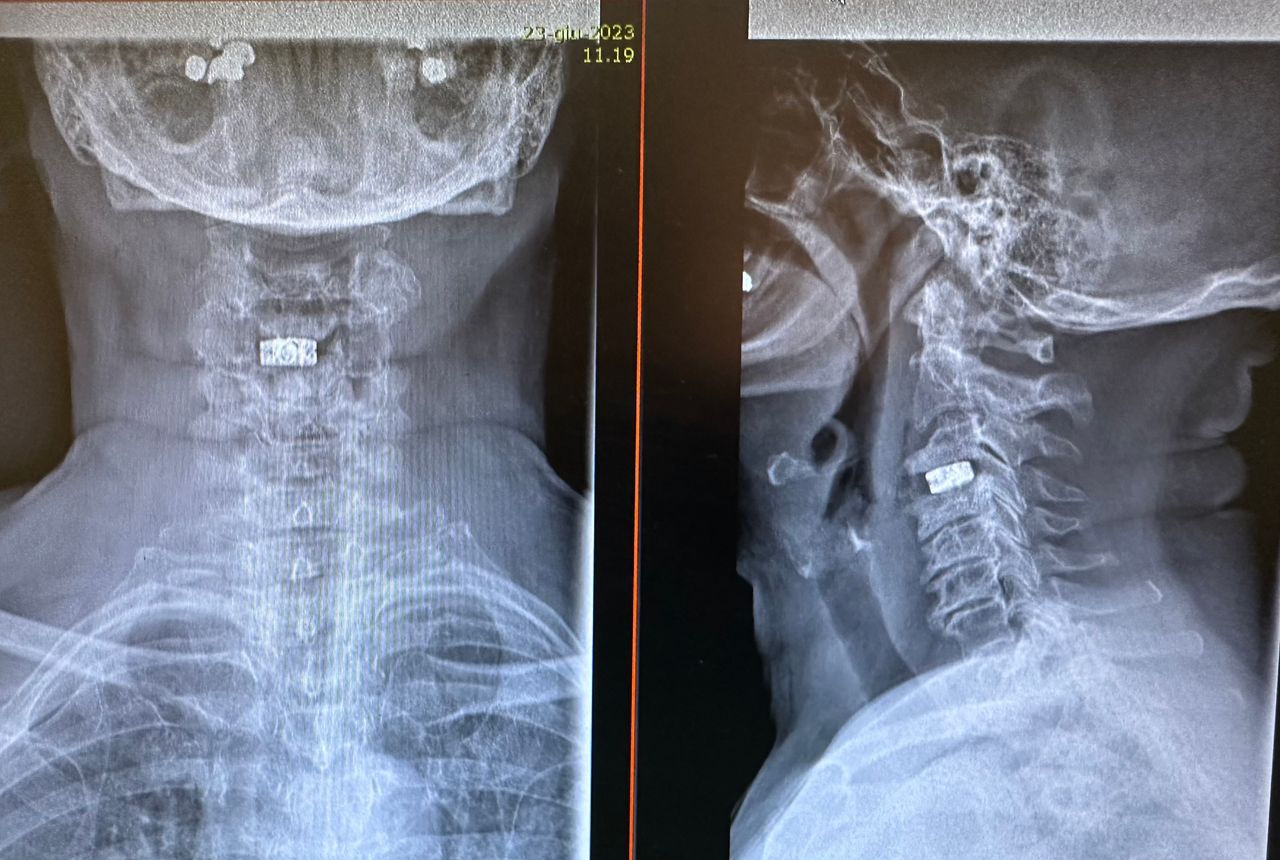

- Microchirurgia vertebrale

Microchirurgia dell’ernia cervicale e lombosacrale con con dimissione entro 24-48 ore

Microchirurgia stenosi del canale vertebrale, stenosi foraminali

- Chirurgia Mininvasiva percutanea vertebrale - stabilizzazioni e artrodesi intersomatiche (per fratture vertebrali, spondilolistesi, instabilità vertebrali, discopatie)